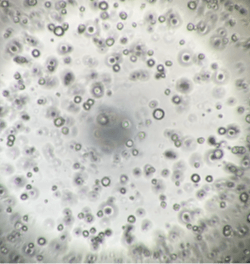

InnoCell(R)プレートシリーズは、体外での細胞培養において、各々の細胞に適した酸素供給を実現できます。その機能により、長期間、元気な細胞を体外で培養できるうえ、スフェロイドの内部で起こる壊死を軽減できるため、正確な医薬品のスクリーニング結果の提供に期待されています。また、これまで体外で培養が難しかった、ヒト膵がん患者由来オルガノイドの増殖性の向上により、個別化医療における患者さんに適した医薬品の早期提供の可能性も期待されています。

さらに、プレートへの薬剤の吸着性が低く、ガラスに匹敵する蛍光観察性能を備えています。試験に供した薬剤が正確に細胞へ作用し、細胞の構造、機能などが可視化できる価値も認められています。